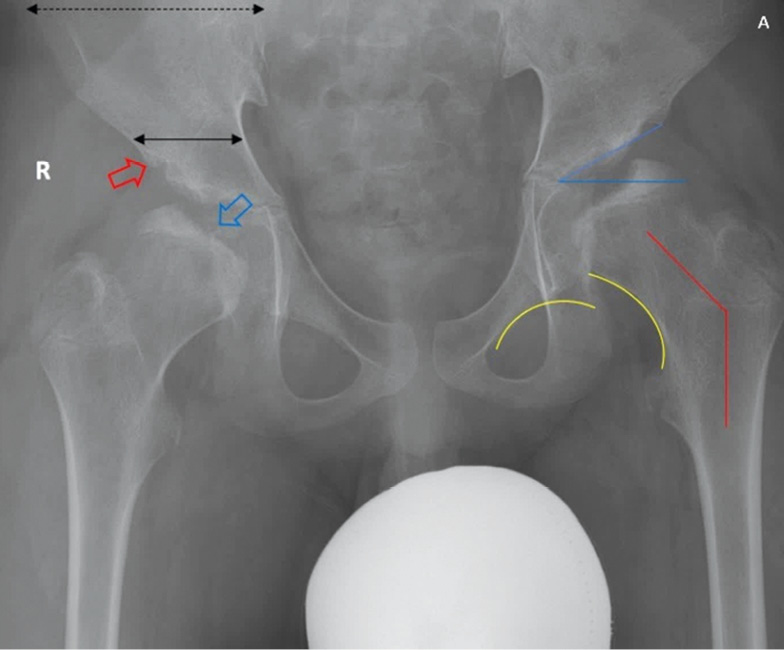

В то же время на рентгенограмме тазобедренных суставов обращают на себя внимание типичные признаки, обозначенные на рис. 4.

Рис. 4. Рентгенограмма тазобедренных суставов в прямой проекции: уплощение и нарушение оссификации эпифизов (голубая стрелка), расширение метафизарных зон, ацетабулярная дисплазия (угол голубого цвета), недостаточная оссификация края вертлужной впадины и головок бедренной кости (красная стрелка), изменение пропорций между шириной крыльев и тела подвздошных костей («симптом Микки-Мауса») (черные стрелки), вальгусная деформация шеек бедренных костей (красная линия), прерывистость линии Шентона (желтые линии)

Дифференциальную диагностику в первую очередь проводили с двусторонней формой болезни Легга – Кальве – Пертеса. Симметричный двусторонний процесс, патогномоничные изменения вертлужной впадины и головок бедренных костей [ацетабулярная дисплазия, недостаточная оссификация края вертлужной впадины и головок бедренных костей, изменение пропорций между шириной крыльев и тела подвздошных костей («симптом Микки-Мауса»), вальгусная деформация шеек бедренных костей], нетипичная для болезни Легга – Кальве – Пертеса клиническая картина позволили заподозрить у пациента МПС [33].